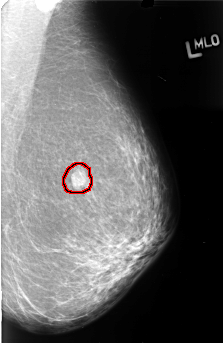

B_3410_1.LEFT_MLO

LEFT_MLO LINES 4456 PIXELS_PER_LINE 2888 BITS_PER_PIXEL 12 RESOLUTION 50 OVERLAY

FILE: B_3410_1.LEFT_MLO.OVERLAY

TOTAL_ABNORMALITIES 1

ABNORMALITY 1

LESION_TYPE MASS SHAPE OVAL MARGINS OBSCURED

ASSESSMENT 3

SUBTLETY 5

PATHOLOGY MALIGNANT

TOTAL_OUTLINES 1

BOUNDARY